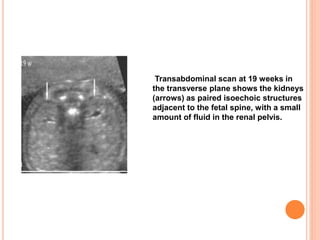

 In the second trimester the kidneys often appear

as isoechoic structures adjacent to the fetal spine

on transabdominal sonography

Transabdominal scan at 19 weeks in

the transverse plane shows the kidneys

(arrows) as paired isoechoic structures

adjacent to the fetal spine, with a small

amount of fluid in the renal pelvis.